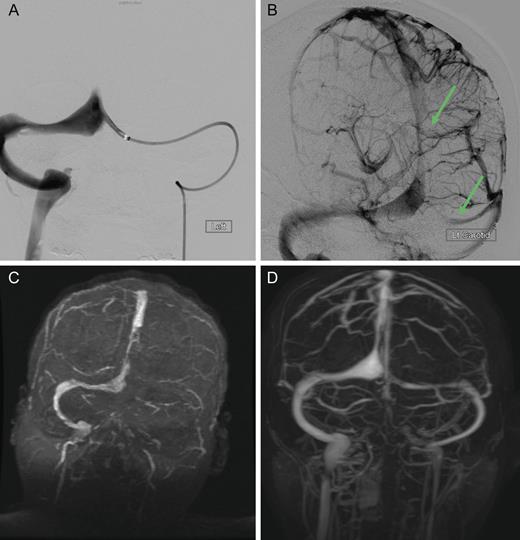

Dural sinus venogram (A) Prior to endovascular mechanical thrombectomy (B) Post mechanical thrombectomy. (C) Pre-intervention MRV demonstrating complete occlusion of the left transverse sinus and near occlusion of the posterior portion of the superior sagittal sinus. (D) Post-intervention MRV demonstrating persistent recanalization of the left transverse and sigmoid sinuses, along with much improved flow in the posterior superior sagittal sinus. Note the recanalization of the left transverse sinus and the much improved flow in the superior sagittal sinus.

The patient was treated emergently with endovascular mechanical thrombolysis with technical success (Fig. 3A and B), followed by systemic anticoagulation therapy. Post-intervention MRV demonstrated persistent recanalization of the left transverse and sigmoid sinuses, along with much improved flow in the posterior superior sagittal sinus (Fig. 3D).